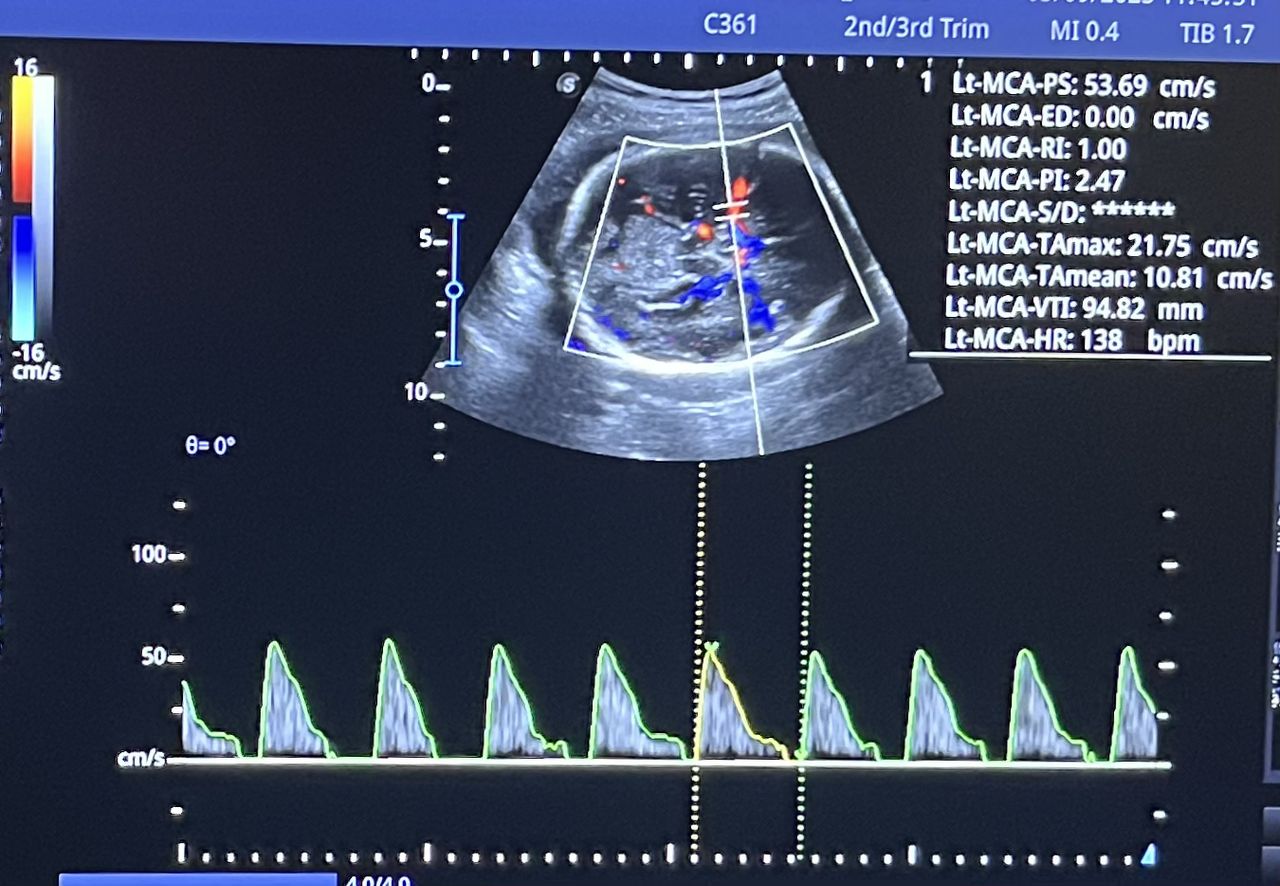

Médico general con 15 años de experiencia, master en enfermedades infecciosas y antibioticoterapia por parte de la Universidad Cardenal Herrera en Valencia, ademas de diversos diplomados en el área de Infectología y Parasitología, Urgencias, Imagenología y Medicina del Trabajo. He laborado en Hospitales y Clínicas en el área de Urgencias, en Laboratorios realizando estudios de Imagen, en especifico ultrasonidos de todo tipo desde básicos hasta avanzados incluidos los obstétricos estructurales, en Secretaría de Salud del Estado de Querétaro realizando ultrasonidos obstétricos para la detección de malformaciones en los tres trimestres del embarazo en diversos centros de salud, como médico de Empresas en el campo de Salud Laboral y actualmente en este consultorio en donde para su mejor atención y siempre buscando integrar la mayoría de las herramientas diagnosticas cuento con equipo de ultrasonido como apoyo en la exploración del paciente o como servicio diagnostico por imagen, realizo ultrasonidos convencionales (hepatobiliar (hígado, páncreas, vesícula y bazo), vías urinarias, ginecológico abdominal y transvaginal, tiroideo, prostático, testicular, pared abdominal) y especializados (dopler obstétrico en los 3 trimestres de embarazo), musculoesquelético en lesiones deportivas. También cuento con un equipo de electrocardiograma de 12 derivaciones para monitoreo completo del funcionamiento cardiaco, espirometria para evaluar la función pulmonar en la consulta, pruebas rápidas que se realizan en consultorio para detectar de forma mas precisa enfermedades infecciosas como Influenza A y B, covid19, infecciones urinarias, dengue, zika, chikungunya. Cuento con diversas vacunas para prevención de enfermedades. Siempre con el objetivo de dar el mejor servicio y atención a su salud. Lo espero en consulta para escucharlo y estudiar su caso de la forma más completa posible, estoy seguro de que tendremos las mejores opciones para su tratamiento. Mi tranquilidad es que usted se vaya con todas sus preguntas e inquietudes resueltas.

• Ultrasonido obstétrico